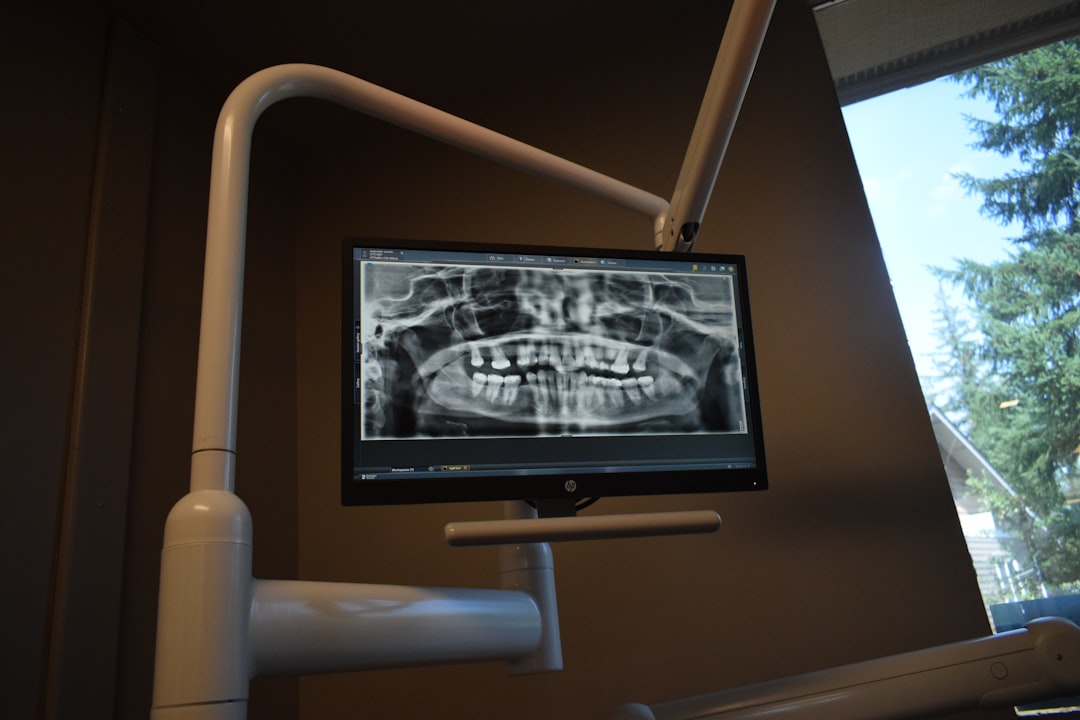

HorliX is a cutting-edge digital radiography and imaging software designed to streamline clinical workflows, enhance patient care, and optimize practice efficiency. Developed by Dents-soft, HorliX offers a comprehensive suite of tools for image acquisition, processing, and storage, making it an ideal solution for dental and medical professionals seeking to transition from traditional film-based radiography to digital imaging.

- Advanced Image Processing: HorliX utilizes sophisticated algorithms to produce high-quality images with enhanced contrast and clarity.